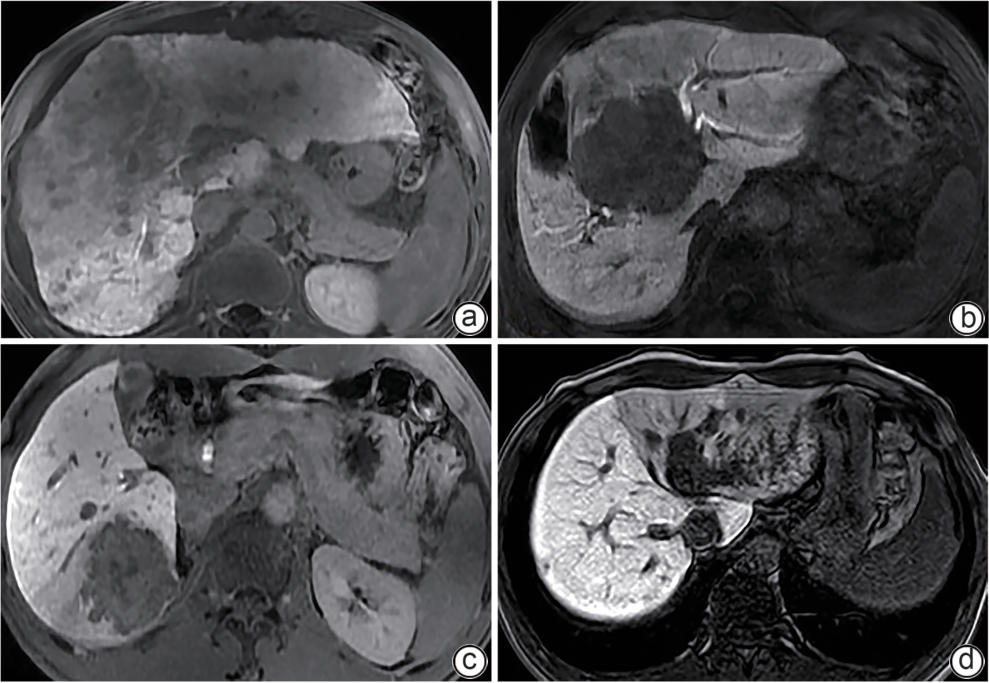

磁共振成像胆道评分和肝肌比值对肝占位患者术前肝储备功能的评估价值

叶彦宏, 陆力坚

2025, 41(9): 1845-1852. DOI: 10.12449/JCH250920

摘要(330) HTML (107) PDF (2327KB)(43)

摘要:

目的  本研究通过构建基于磁共振胆道相关参数和肝肌比的Nomogram预测模型,探讨该预测模型在肝占位患者术前肝储备功能评估中的应用价值。  方法  收集2022年4月—2024年4月在广西医科大学附属武鸣医院住院并拟行手术的112例肝占位患者的临床资料和钆塞酸二钠增强MRI的影像资料。根据肝损伤程度,将患者分为肝功能代偿良好组(Child-Pugh A级65例)、肝功能失代偿组(Child-Pugh B级42例,C级5例)。测量两组患者不同增强扫描时期的肝肌比、胆总管相对强化程度及胆道评分,并运用单因素和多因素Logistic回归分析筛选独立的预测因素,进而构建Nomogram模型。同时绘制受试者操作特征曲线(ROC曲线)、校正曲线、决策曲线,以评估模型的区分度、准确性和临床应用价值。计量资料符合正态分布的数据两组间比较采用成组t检验;符合偏态分布的数据两组间比较采用Mann-Whitney U检验。计数资料两组间比较采用χ2检验。  结果  两组间肝胆期5 min肝肌比(Z=-3.99)、肝胆期10 min肝肌比(Z=-4.39)、肝胆期15 min肝肌比(Z=-4.23)、肝胆期20 min肝肌比(Z=-5.40)、胆总管相对强化程度(Z=-4.85)及胆道评分(t=7.99)比较差异均有统计学意义(P值均<0.001)。多因素Logistic回归分析显示,肝胆期10 min肝肌比(OR=0.63,95%CI:0.44~0.90)、肝胆期20 min肝肌比(OR=0.38,95%CI:0.17~0.82)及胆道评分(OR=0.17,95%CI:0.07~0.39)是术前诊断肝功能失代偿的独立影响因素(P值均<0.05)。基于肝胆期10 min肝肌比、肝胆期20 min肝肌比及胆道评分建立的Nomogram模型术前诊断肝功能失代偿的ROC曲线下面积为0.905(95%CI:0.849~0.960),敏感度为78.7%,特异度为89.2%。  结论  基于肝胆期10 min肝肌比、肝胆期20 min肝肌比及胆道评分构建的列线图模型,在术前能有效评估拟接受手术治疗的肝占位患者的肝储备功能状态。